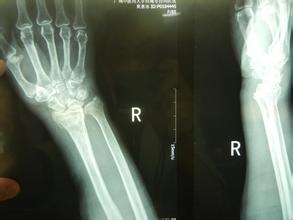

桡骨是人体前臂双骨之一,位于前臂外侧,大拇指一侧,分为一体和两端。是前臂长骨之一;蛙、蟾蜍等动物的桡骨与尺骨愈合成桡尺骨。骨密度仪厂家山东国康为您讲述桡骨引起的桡骨远端骨折。

1、跌倒后腕关节处于背伸,手掌着地,重力集中于桡骨远端松质骨处而引起骨折。老年人由于骨质疏松,轻微外力即可造成骨折,大多数是粉碎骨折。这是最常见的一种桡骨远端骨折的原因。

2、跌倒后手背着地,骨折远端向掌侧及尺侧移位。这种情况比较少见。

3、跌倒后手掌或手背着地,重力向上传递后近排腕骨撞击引起桡骨关节面骨折,桡骨下端掌侧或背侧形成关节面软骨的骨折块,骨块常向近侧移位,引起腕关节脱位。青壮年发生几率高。

桡骨远端骨折应及时去正规医院就医,根据骨折的严重性合理的治疗。骨折治疗期间患者要注意肩、肘及手指的活动锻炼,锻炼要适量。尤其老年人通过锻炼预防肩关节僵硬。同时还要注意桡骨远端骨折的并发症。部分患者愈合较好,而损伤较重患者或者治疗不当容易引起骨骺早期闭合者,长期不矫正就可出现尺骨长、桡骨短,手腕桡偏的曼德隆样畸形。此并发症给患者身心带来痛苦,因此应及时矫正和处理。